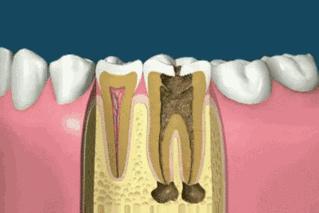

插着根管的病牙

朋友A牙齿情况不是很好,蛀牙很多,外观看着是不错,等牙医钻开才发现已经龋坏到牙髓,所以得杀神经。A杀了两颗牙神经,第一颗牙打了麻药还是疼,却在治第二颗牙时完全没感觉。那个美女牙医说A的第二颗牙已经全部坏死,都没感觉了,连麻药都省了。

PS:传统的根管治疗仅靠医生经验操作,难以保留未受感染的牙髓,也不能一次性成功完成根管治疗,基本根管治疗后的牙齿都是死髓牙了。

死髓牙